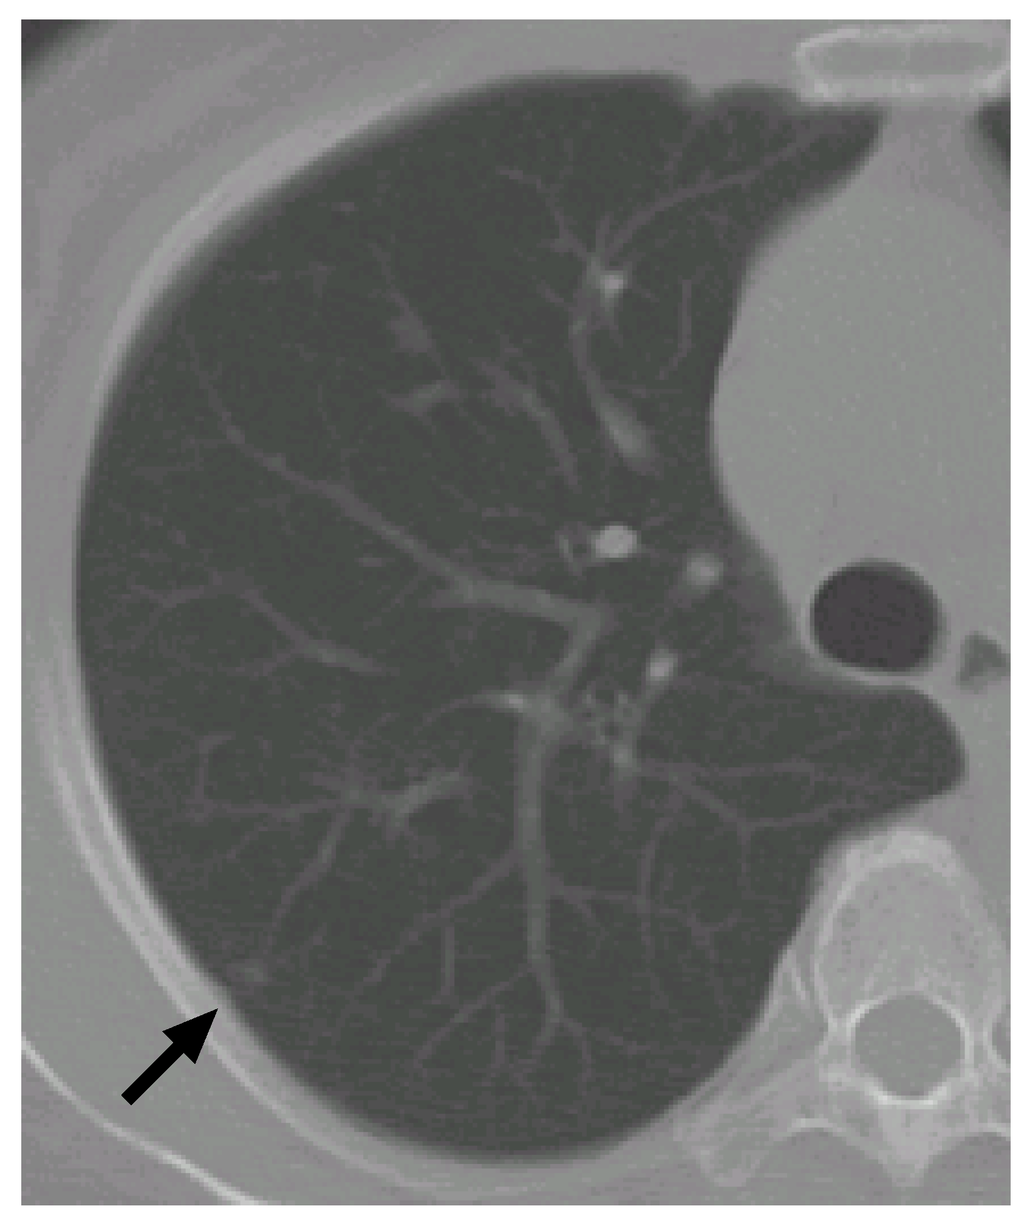

7.2. Case 2

Figure 9 shows another CT scan with a nodule. Figure 10 shows its VOI and templates, and Figure 11 the most likely object models. The posteriori probabilities are 0.121, 0.100 and 0.101, and the ratio is 1.20, that is larger than the threshold. Although the nodule is small (its diameter is approximately 3.8 mm), it is correctly determined to be a nodule.

Figure 9. The arrow indicates another nodule.